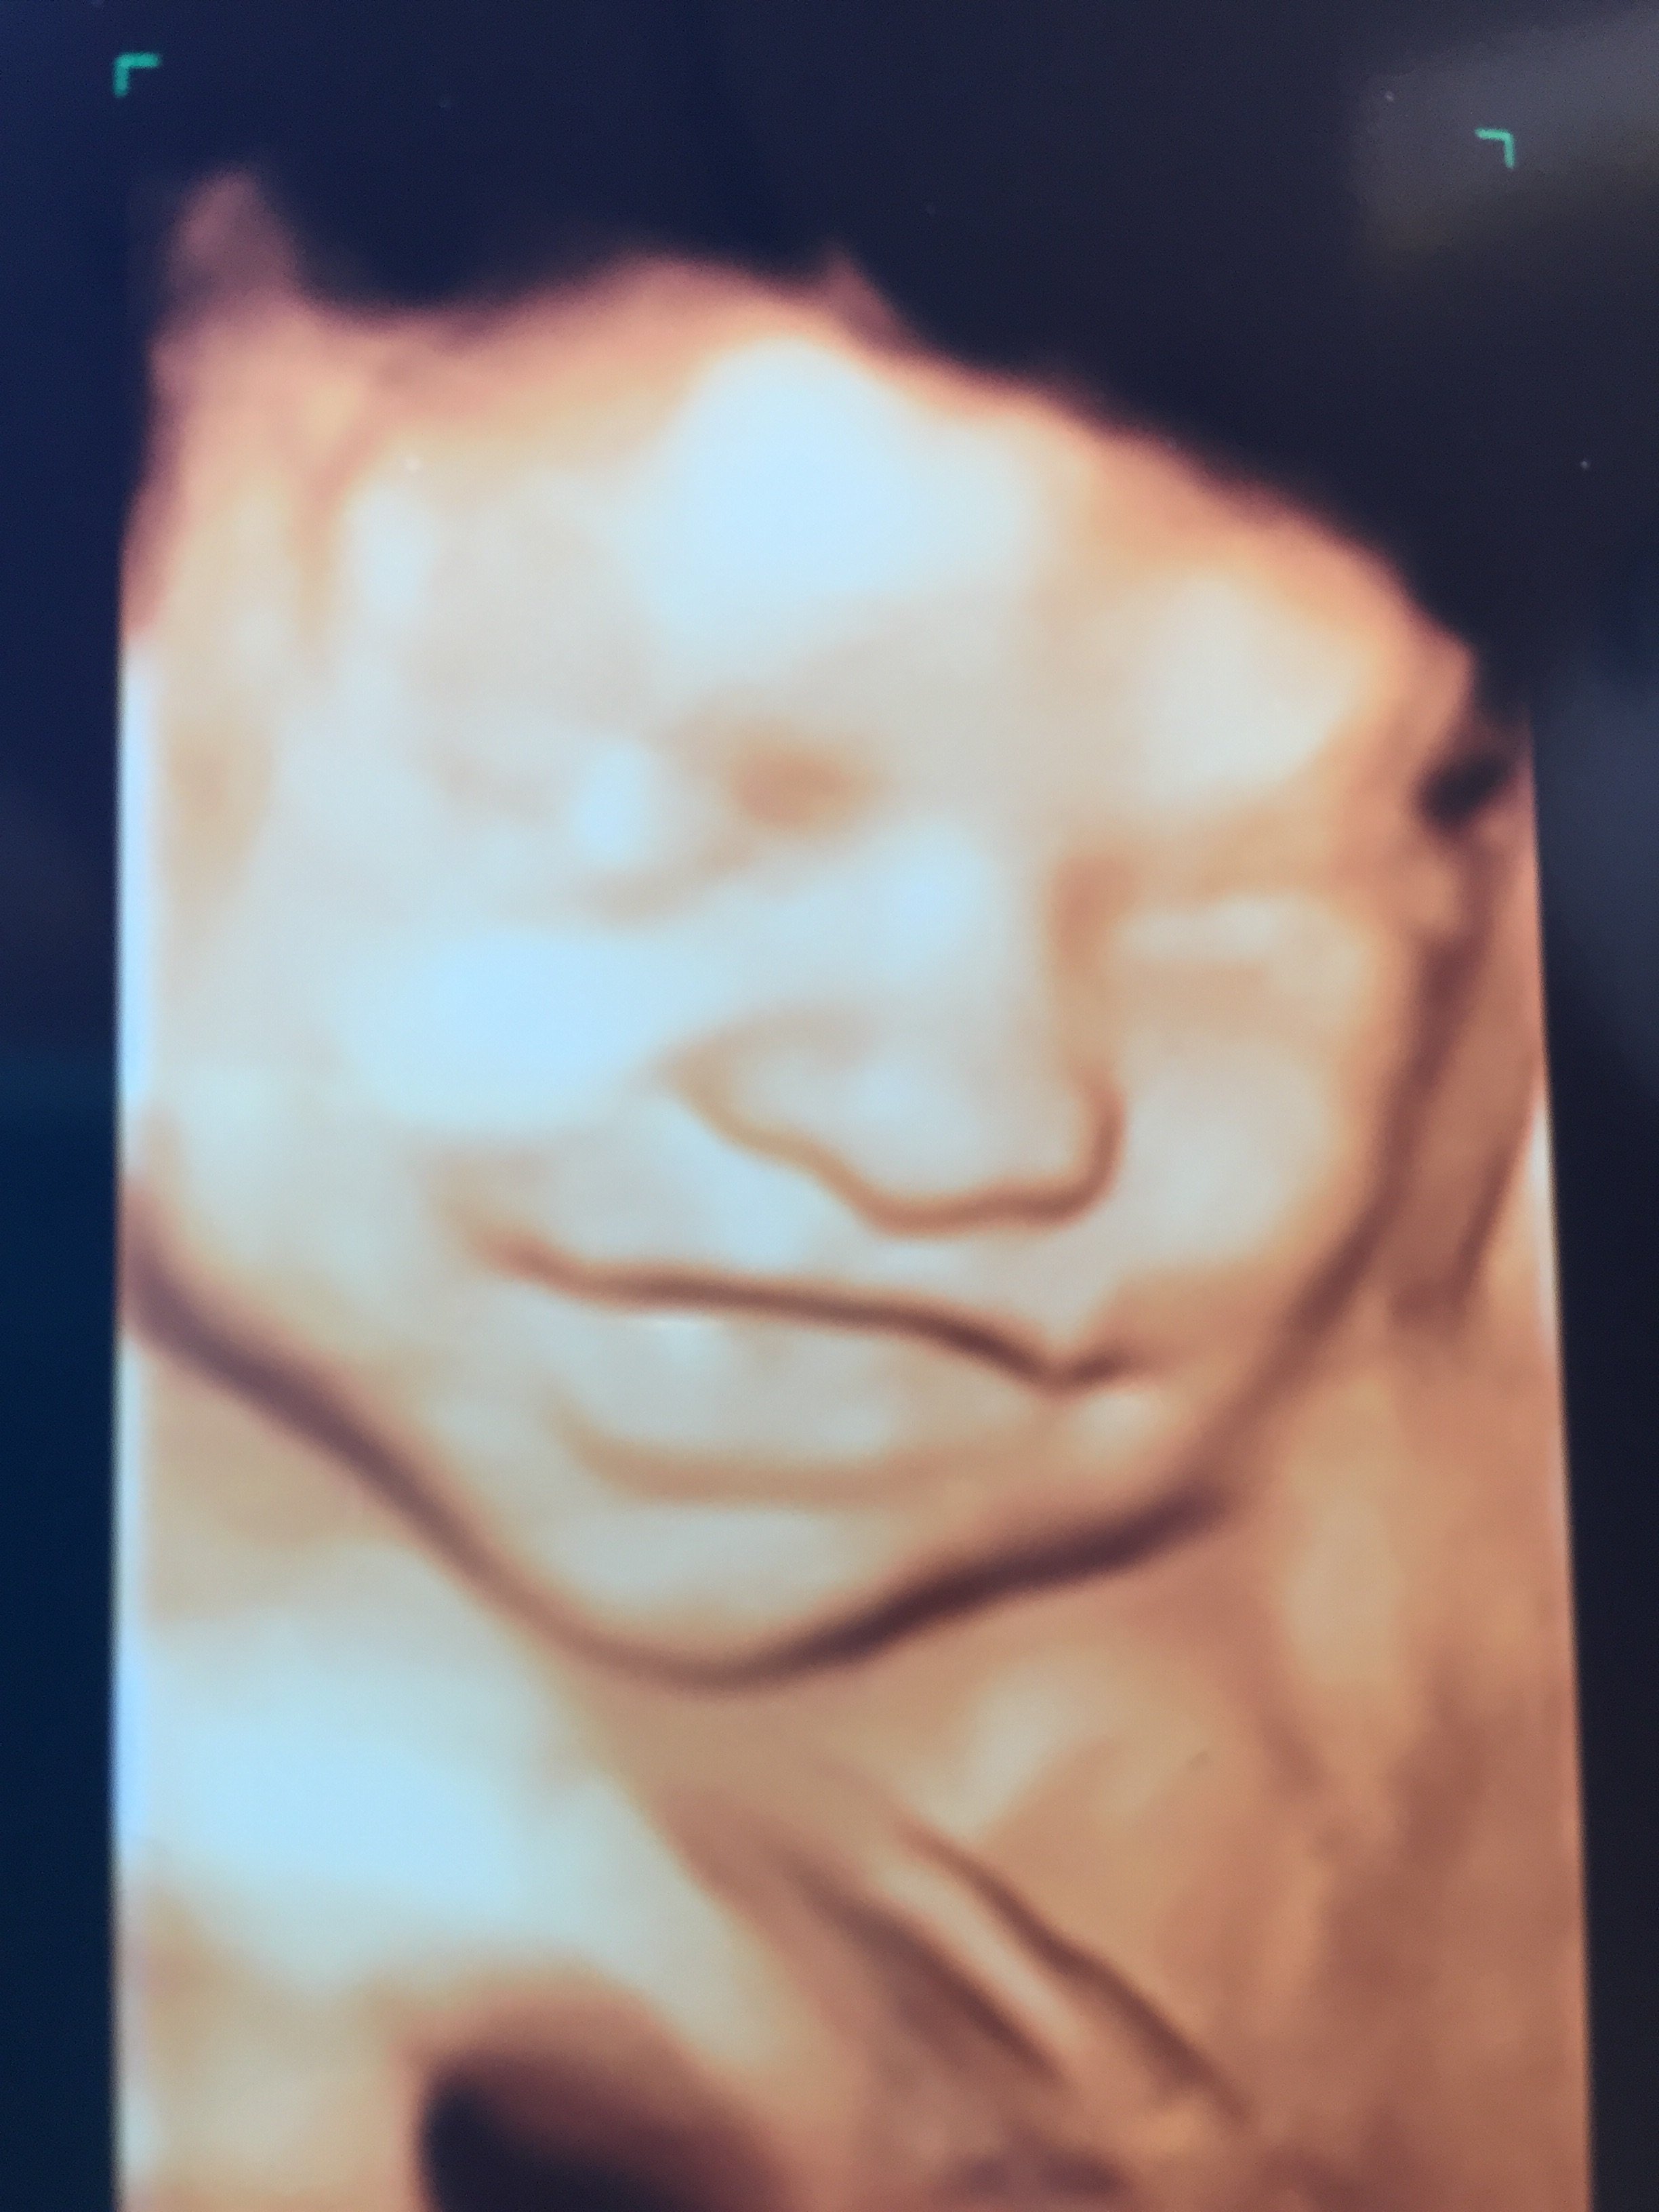

Re: 12 weeks & 2 days to go!